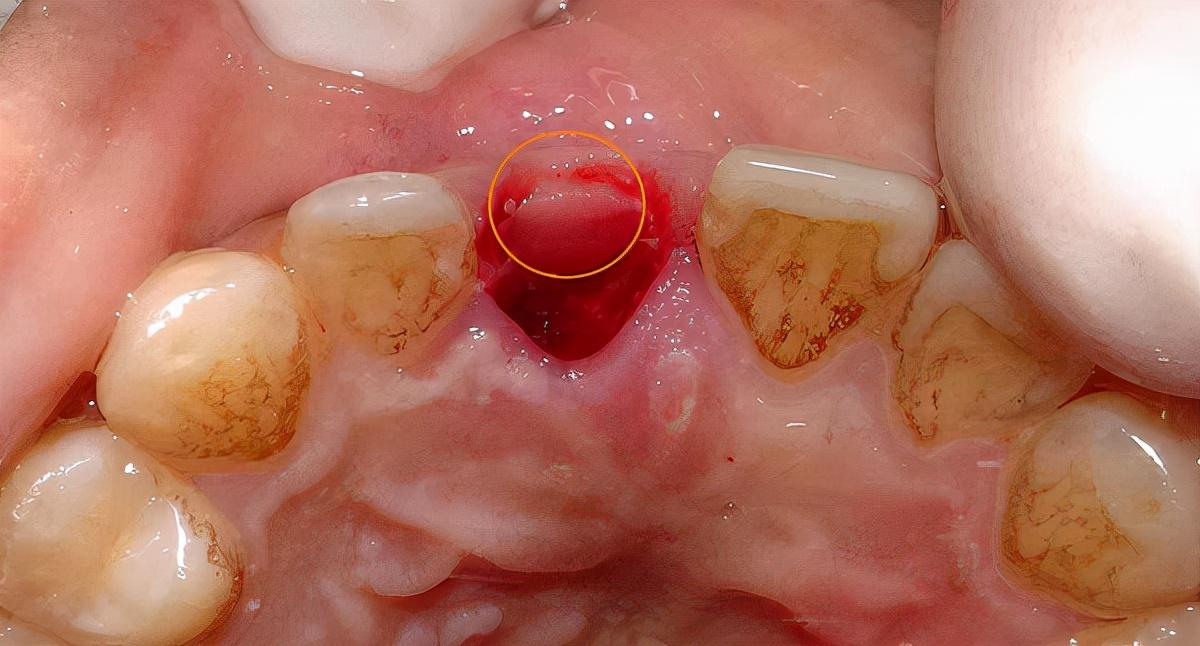

口內(nèi)照:

備洞,準(zhǔn)備植入種植體